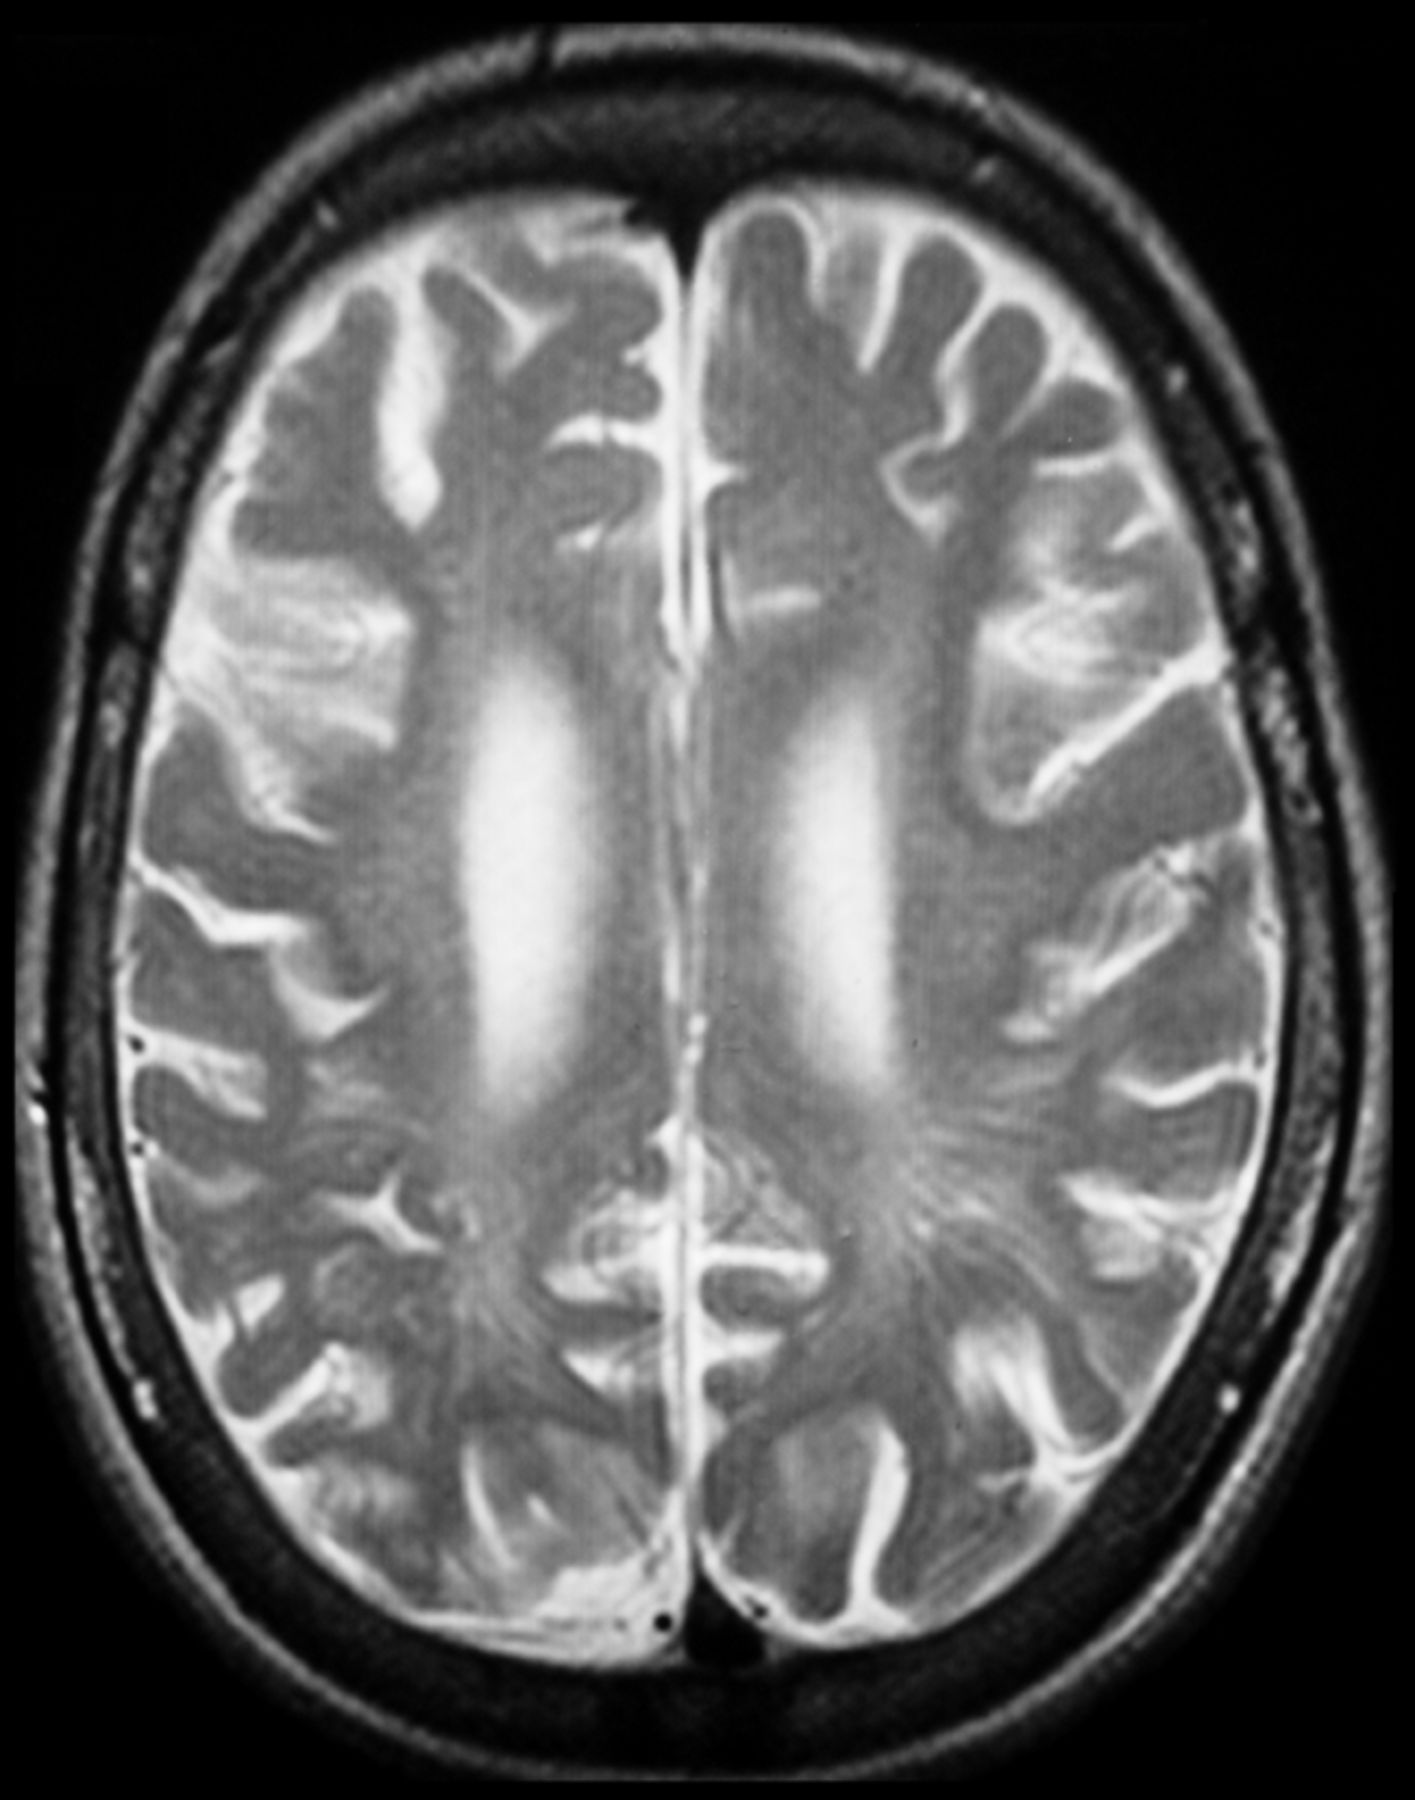

Brain axial T2-weighted image (TR/TE, 4000/99 ms) of a 9-year-old patient with MPS II, demonstrating ventricular dilation and enlargement of the cortical sulci. WMA and disperse cystic lesions in the periventricular area are also noted.

WMA mainly consist of diffuse or focal areas of prolonged T1 and T2 relaxation times. These intensity changes are usually diffuse in patients with MPS III, while they are patchily distributed in other types of MPS.18 The most commonly affected region is the periventricular white matter,12,15 though signal-intensity abnormalities may appear in all parts of the cerebrum, affecting various brain lobes and subcortical regions.19,24 Concerning deep gray matter signal-intensity abnormalities, changes have been described in the region of the basal ganglia.16 As a result of T2-weighted images showing abnormally high signal intensity, diminished contrast between the cerebral cortex and underlying white matter is usually demonstrated.16,27

Differentiation between communicating hydrocephalus and brain atrophy is a demanding task because both conditions share common clinical and neuroradiologic features (enlarged ventricular and subarachnoid spaces). This is actually the reason that some authors merged data regarding those 2 situations and considered them as one.22 Nevertheless, Lee et al10 defined cerebral atrophy as the presence of dilated brain sulci. It represents one of the most prevalent MR imaging features in patients with MPS II12,18,20⇓–22,24,26 and IIIB,18,21,28,40,41 while it is also described in MPS I,11,12,21,43 IIIA,39,45 IIID,29 and VI.21 Cerebral atrophy is predominantly cortical and diffuse18 (Figs 1⇑⇑–4) and may be symmetric or asymmetric.12,26 In relation to the asymmetry, no explanation is currently valid. Matheus et al12 hypothesized that it may be the result of irregular GAG storage or reabsorption of the CSF. The pathophysiology of brain atrophy remains unclear. It is probably the result of neuronal death and gliosis induced by the accumulation of mucopolysaccharides,10 though other theories such as microglial activation, enlargement of CSF spaces, ectopic dendritogenesis, and neuroaxonal dystrophy have been proposed.20,46,47